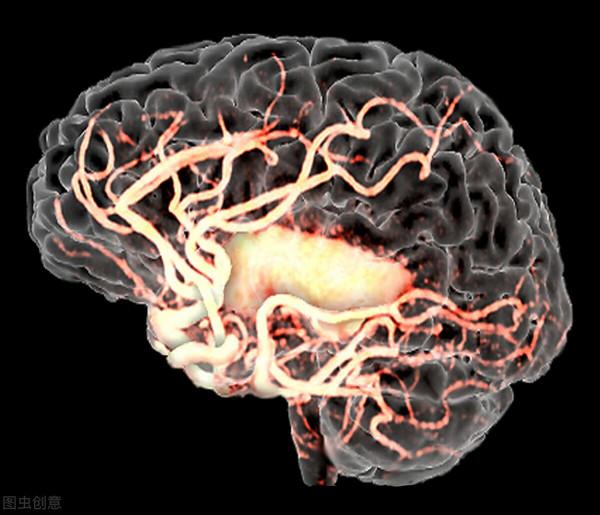

很多人對腦卒中並不是很瞭解,其實說到他的另一個名詞,你可能就有感覺了,那就是腦血管意外。

很多急性的腦血管疾病會引起腦功能障礙,這些都是腦卒中的範疇,在臨床當中這種疾病是經常發生的。

腦卒中包括很多種,比如腦出血、腦血栓形成和腦栓塞,其實這些都屬於腦卒中。